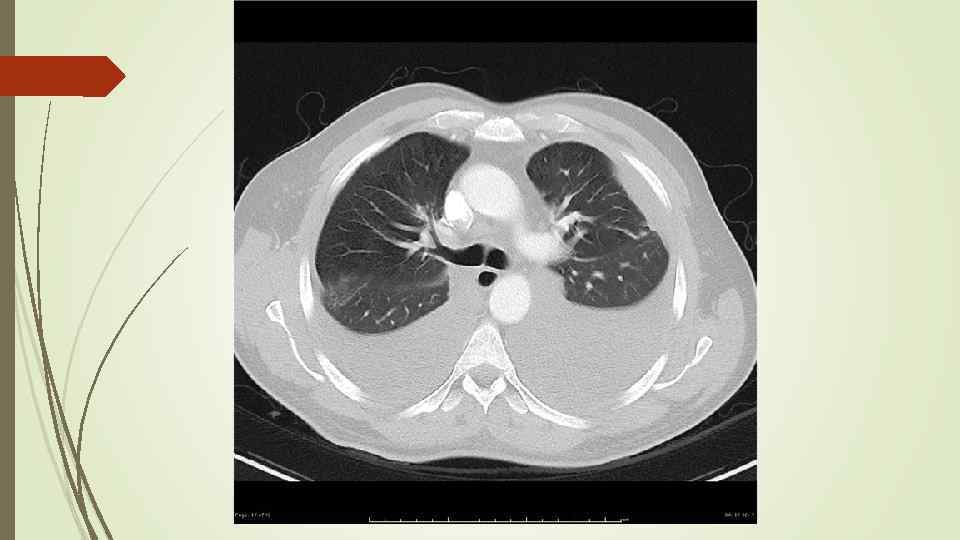

Бронхопневмония Характерно наличие двухсторонних множественных очаговых теней. Контуры очагов нечеткие, интенсивность тени небольшая. Инфильтрация неоднородна. Мелкие, малоинтенсивные очаги не всегда выявляются на снимках. Легочный рисунок усилен на всем протяжении легких. Корни расширены, не структурны. Как правило, отмечается реакция плевры, могут быть и экссудативные плевриты.

Бронхопневмония Характерно наличие двухсторонних множественных очаговых теней. Контуры очагов нечеткие, интенсивность тени небольшая. Инфильтрация неоднородна. Мелкие, малоинтенсивные очаги не всегда выявляются на снимках. Легочный рисунок усилен на всем протяжении легких. Корни расширены, не структурны. Как правило, отмечается реакция плевры, могут быть и экссудативные плевриты.

bronhopneumoni

bronhopneumoni

bronhopneumonie miliar

bronhopneumonie miliar